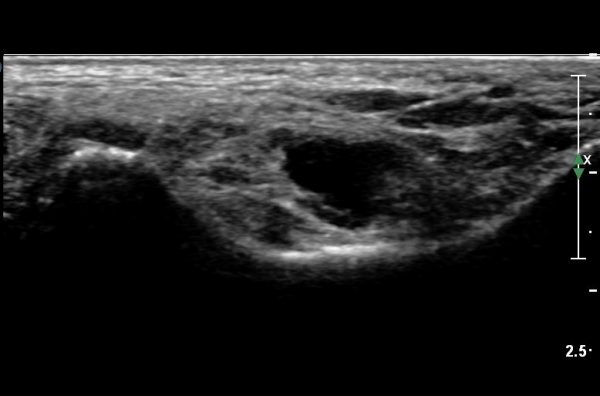

¹ß¸ñÅͳΠȾ´Ü¸é°Ë»ç¿¡¼­ ³»Ãø º¹»ç»À ³»Ãø¿¡ Èİæ°ñ°Ç, ¹ß°¡¶ô±¼°î°Ç°ú ¾öÁö¹ß°¡¶ô±¼°î°Ç

»çÀÌ¿¡¼­ Èİæ°ñ½Å°æÀÌ °üÂûµÇ°í ½Å°æÀÇ Ç¥Ãæ¿¡ µ¿¸Æ°ú Á¤¸ÆµéÀÌ °üÂûµÈ´Ù(»çÁø 1).